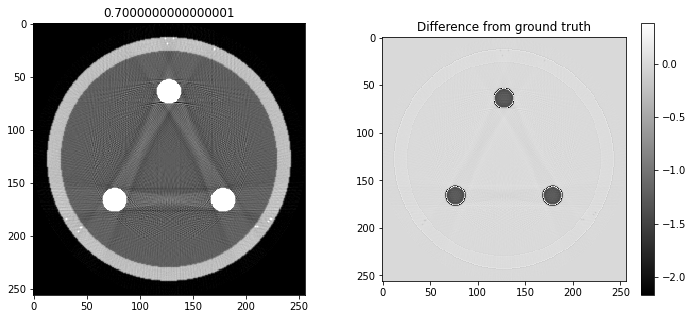

# Question 12

search = np.linspace(0,1,11)

for alpha in search:

rec = out+alpha*reproj

f,ax = plt.subplots(1,2,figsize=(12,5))

ax[0].imshow(rec,vmin=0,vmax=0.5)

ax[0].set_title(alpha)

im = ax[1].imshow(img[80]-rec)

f.colorbar(im,ax=ax[1])

ax[1].set_title('Difference from ground truth')

plt.show()